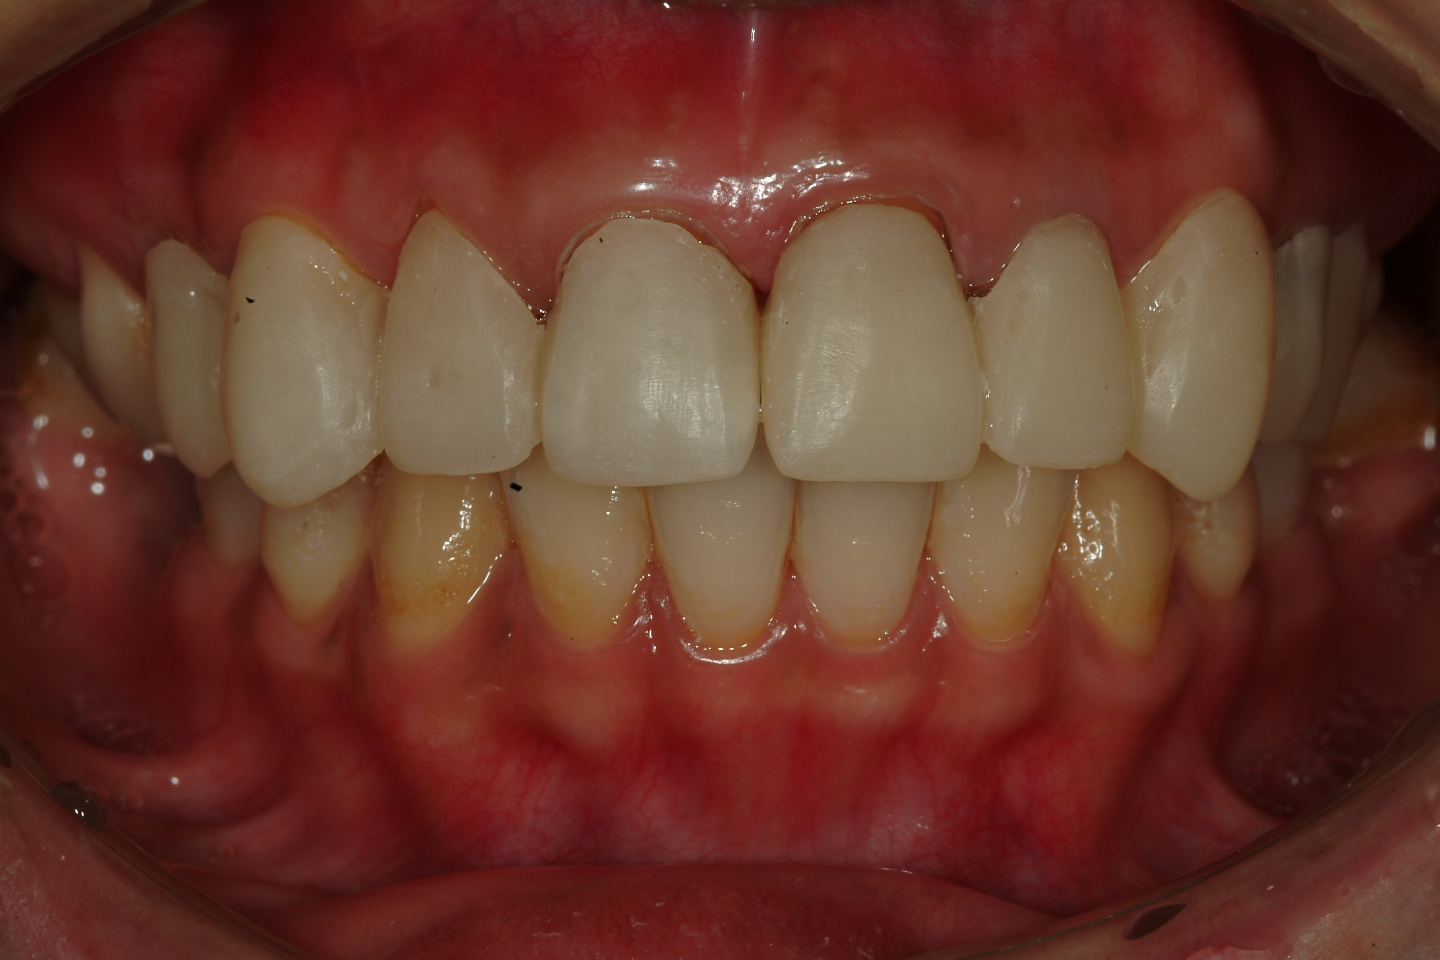

圖一 |

患者的經過診斷,問題如下:(圖二)

一、上頷右上第四小臼齒到左上第五小臼齒皆有不良補綴物,須移除。

二、部分前牙根尖病變 , 根管治療須重新完成 .

三、以假牙方式改變前牙外型

圖二 |